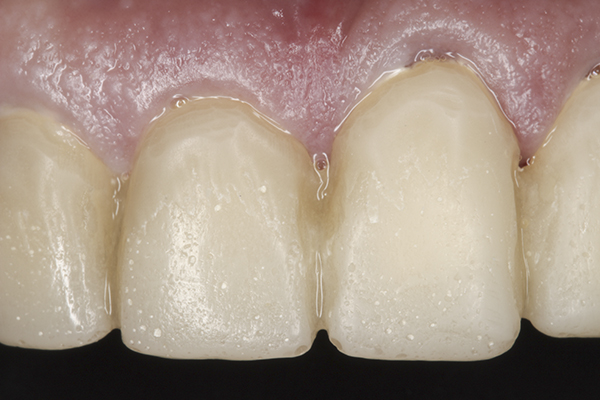

(39.) Postoperative anterior, close-up view.

Figure 39